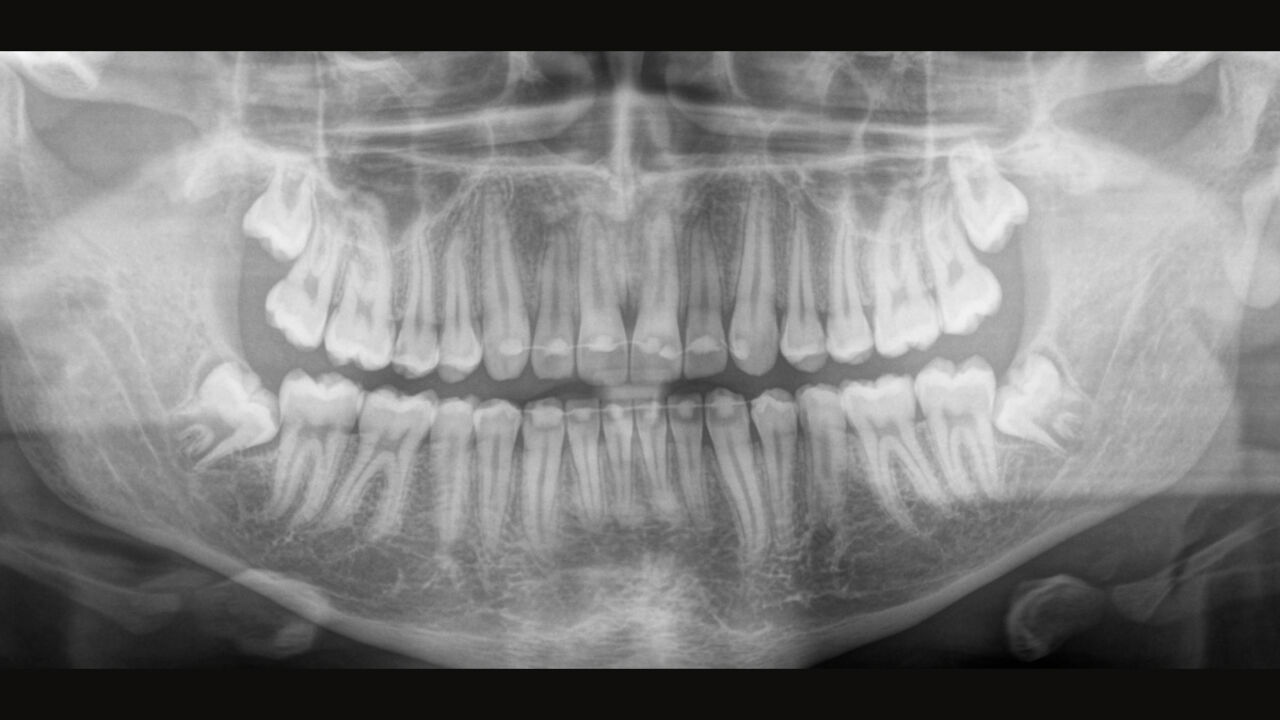

De juiste focus is cruciaal voor hoogkwalitatieve panoramische röntgenfoto's. Met de autofocusfunctie ontvangt u automatisch een beeld met de best mogelijke scherpte. Dentsply Sirona Imaging-apparaten maken enkele duizenden afzonderlijke beelden in één cyclus en identificeren automatisch de gebieden waar de kaak optimaal is gepositioneerd. Zonder extra handmatige stappen worden deze beelden vervolgens weergegeven in een definitieve scherpe afbeelding.

Slechts enkele delen van het beeld zijn scherp, terwijl andere gebieden wazig zijn.

Het systeem detecteert de relevante gebieden van enkele duizenden afzonderlijke beelden in één cyclus en identificeert automatisch de gebieden waar de kaak optimaal is gepositioneerd.

Scherpe beelden.